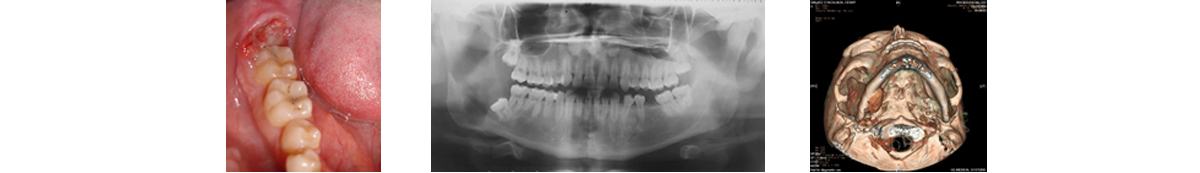

El tratamiento de grandes tumores mandibulares, reemplazos de la articulación temporo mandibular (ATM) por disfunciones avanzadas, u otras patologías conlleva a la resección quirúrgica mandibular en bloque de un segmento, así como secuelas de infecciones y trauma de alta energía. Situaciones clínicas que ocasionan una alteración anatómica y funcional del paciente con implicaciones estético-funcionales que necesitan meticulosidad en la reconstrucción de los defectos con la combinación de injertos óseos libres, prótesis de ATM, distracción ósea e implantes cigomáticos